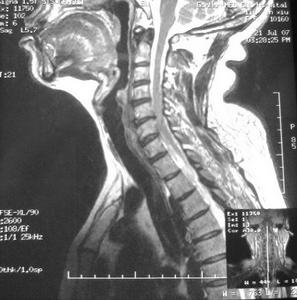

脊髓栓系綜合徵CT圖診斷檢查

脊髓栓系綜合徵影像脊髓栓系綜合徵的診斷依據:①疼痛範圍廣泛,不能用單一根神經損害來解釋;②成人在出現症狀前有明顯的誘因;③膀胱和直腸功能障礙,經常出現尿路感染;④感覺運動障礙進行性加重;⑤有不同的先天畸形,或曾有腰骶部手術史;⑥MRI和(或)CT椎管造影發現脊髓圓錐位置異常和(或)終絲增粗。

1.MRI是診斷脊髓栓系綜合徵最佳和首選的檢查手段。它不僅能發現低位的脊髓圓錐,而且能明確引起脊髓栓系綜合徵的病因。

2.CT椎管造影CT脊髓造影能顯示脂肪瘤、脊髓圓錐、馬尾神經和硬脊膜之間的關係,對制訂手術入路有指導作用。另外,CT能顯示骨骼畸形、脊柱裂、椎管內腫瘤等。但是CT診斷脊髓栓系綜合徵的敏感性和可靠性不如MRI,CT椎管造影又屬有創性檢查,因此,對典型脊髓栓系綜合徵病人,MRI診斷已足夠。由於MRI和CT各有其優缺點,對複雜脊髓栓系綜合徵或MRI診斷可疑者,還需聯合套用MRI和CT椎管造影。